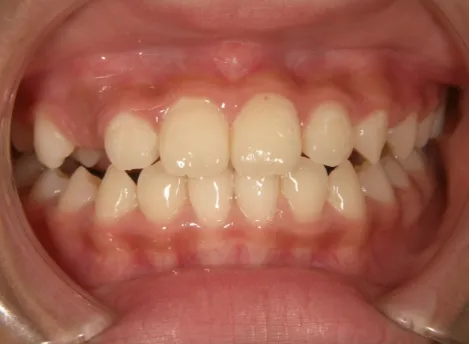

治療後⑩高2:17y7m 抜歯治療終了

口元の治療前後:15y5m→17y7m スッキリしました